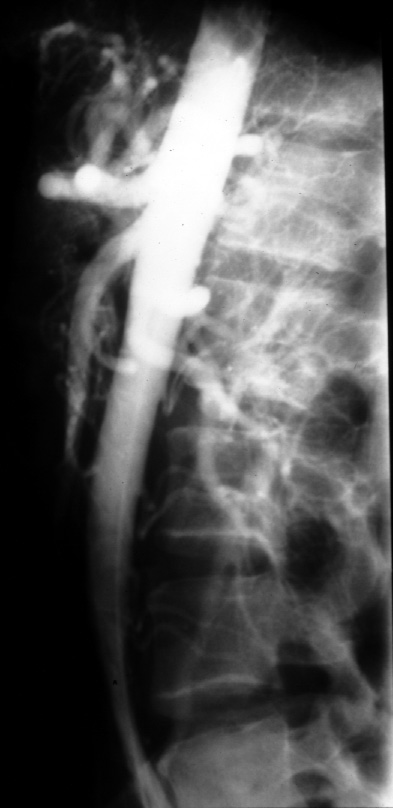

Radiology of Abdomen, Pelvis, and Perineum -- Normal Anatomy Arteriogram

(Lateral)

Identify the following arteries -- celiac axis, superior mesenteric (SMA)